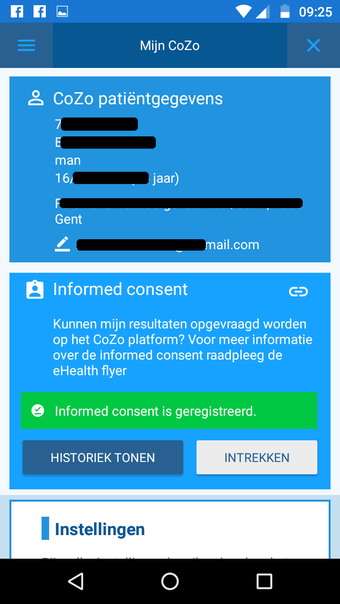

CoZo est une application de santé électronique qui permet aux patients et aux médecins de communiquer entre eux et de partager des informations médicales. Elle a été développée pour répondre aux problèmes du système de santé actuel, caractérisé par un manque de communication entre les patients, les médecins et les autres professionnels de la santé.

CoZo permet aux patients de prendre une part active dans leur propre santé et d'être traités comme des participants actifs dans le processus de soins. Les patients peuvent utiliser l'application pour enregistrer leurs données de santé, qu'ils peuvent ensuite partager avec leurs médecins. Les médecins peuvent utiliser l'application pour enregistrer l'historique médical de leurs patients, poser un diagnostic et suggérer un plan de traitement.